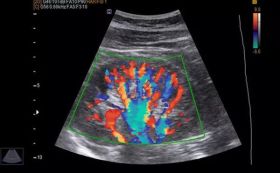

Color Doppler is a technique in which colors superimposed on an image of a blood vessel indicate the speed and direction of blood flow in the vessel. Colour doppler test is a type of ultrasound test.